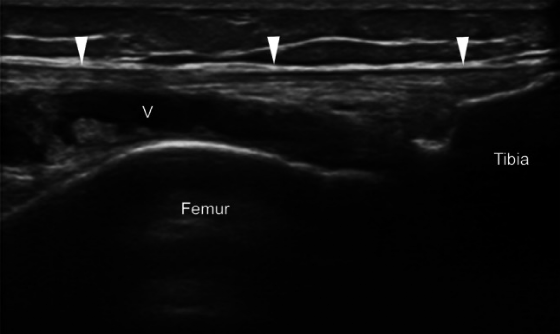

髂胫束综合征或摩擦综合征是膝关节外侧过度使用的疾病。它在运动员(例如跑步和自行车)群体中高发。超声影像作为一种高性价比的成像方式,能够以高分辨率、动态评估以及与对侧健康侧进行比较来显示浅表软组织结构,对于评估髂胫束综合征具有重要参考价值。

- 关于第一点的“摩擦说”:与髂胫束在涉及重复膝关节屈伸的活动中来回摩擦股骨外上髁有关,从而导致髂胫束摩擦和邻近软组织发炎。多年来,这一病因一直存在争议,特别是关于髂胫束运动的方向和程度。然而,一项超声研究表明,在膝关节伸展和屈曲期间,髂胫束相对于股骨外上髁沿前后方向移动,因此支持摩擦作为病因学因素的核心作用。